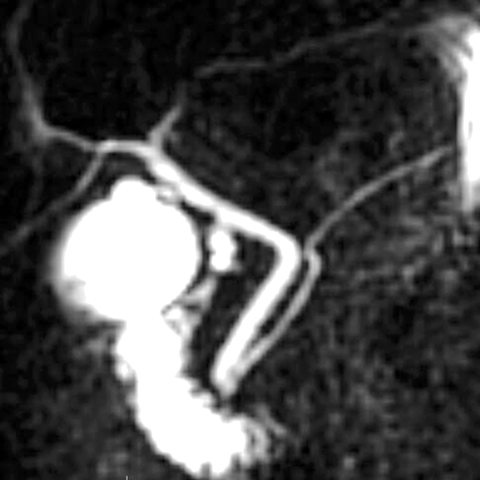

MR Cholangio-Pancreatogram